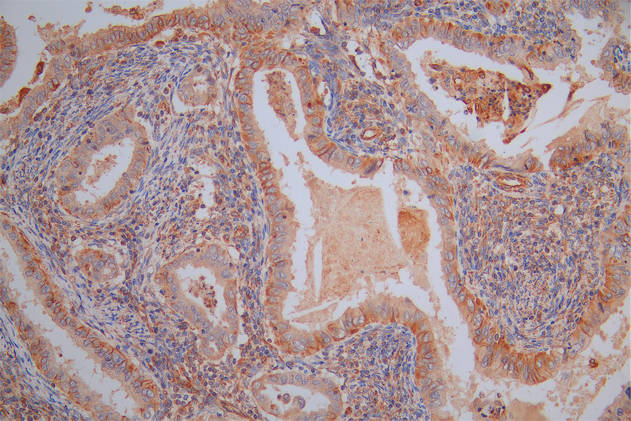

Immunohistochemistry of paraffin-embedded human lung tissue using CSB-PA814217LA01HU at dilution of 1:100